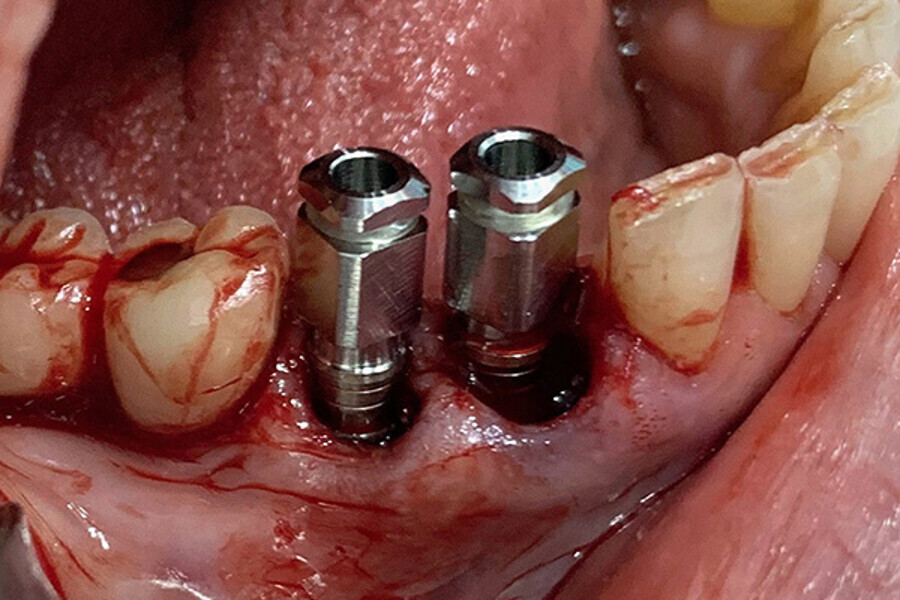

Figs. 9. Colocación de 2 implantes post-extracción en posiciones del 43 y 44 y control radiográfico post-extracción.

Figs. 10. Colocación de 2 implantes post-extracción en posiciones del 43 y 44 y control radiográfico post-extracción.